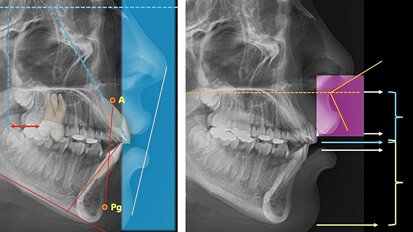

Mientras los escáneres intraorales reconstruyen superficies mediante barrido secuencial (luz estructurada, triangulación, confocalidad), la fotogrametría basa su reconstrucción en correspondencias globales entre imágenes, lo que reduce el error acumulativo típico de la posición espacial de los implantes en arcos largos. El CBCT aporta información volumétrica ósea imprescindible para la planificación, pero no ofrece la resolución superficial necesaria para la adaptación protésica; la integración multimodal (fotogrametría + CBCT) permite vincular con precisión la interfaz protésica con la anatomía ósea (1,3,10).

Según las normas internacionales, la exactitud se descompone en veracidad (cercanía al valor de referencia) y precisión (reproducibilidad) (11). En implantología las métricas se expresan en desviaciones lineales en micras (μm) y angulares (grados). Para prótesis fijas se consideran deseables desviaciones lineales inferiores a 100-150 μm y angulaciones compatibles con conexiones estándar para minimizar tensiones y complicaciones, como en el caso de implantes múltiples en arcos totalmente edéntulos donde se busca generar restauraciones pasivas y de ajuste cercano a la perfección (12-14).

Los estudios in vitro muestran que, en condiciones controladas, la fotogrametría logra errores lineales medios menores de 100 μm y desviaciones angulares <1° cuando se usan cámaras de alta resolución y scanbodies rígidos; en arcos parciales, los IOS modernos y la fotogrametría ofrecen resultados comparables, pero en arcos completos la fotogrametría suele preservar mejor la veracidad al evitar acumulación de error (15-22).

La literatura científica reporta resultados prometedores en rehabilitaciones All-on-4 / All-on-6 y en fabricación de barras y estructuras rígidas, con reducción de ajustes y reprocesos cuando hay protocolos estandarizados y se utilizan laboratorios familiarizados con esta técnica (23-27). No obstante, se necesitan más ensayos controlados aleatorios y estudios longitudinales multicéntricos que asocien métricas de precisión con resultados restaurativos y biológicos a largo plazo (28-30).

El estudio pionero de Marta Revilla-León, de la Universidad de Washington en Seattle, sobre la precisión del escaneo de implantes de arco completo con sistemas de fotogrametría intraoral y extraoral (1) comparó la precisión de los sistemas fotogramétricos intraorales y extraorales con un escaneo tradicional, evaluando desplazamientos lineales y angulares en múltiples implantes. En condiciones controladas, los sistemas extraorales mostraron mayor veracidad respecto a algunos sistemas intraorales fotogramétricos; sin embargo, las diferencias clínicas dependieron de la calidad de los scanbodies, la calibración de los escáneres y los protocolos de captura. El trabajo enfatiza la necesidad de estandarizar procedimientos y criterios para permitir hacer comparaciones válidas entre diferentes tecnologías (31).